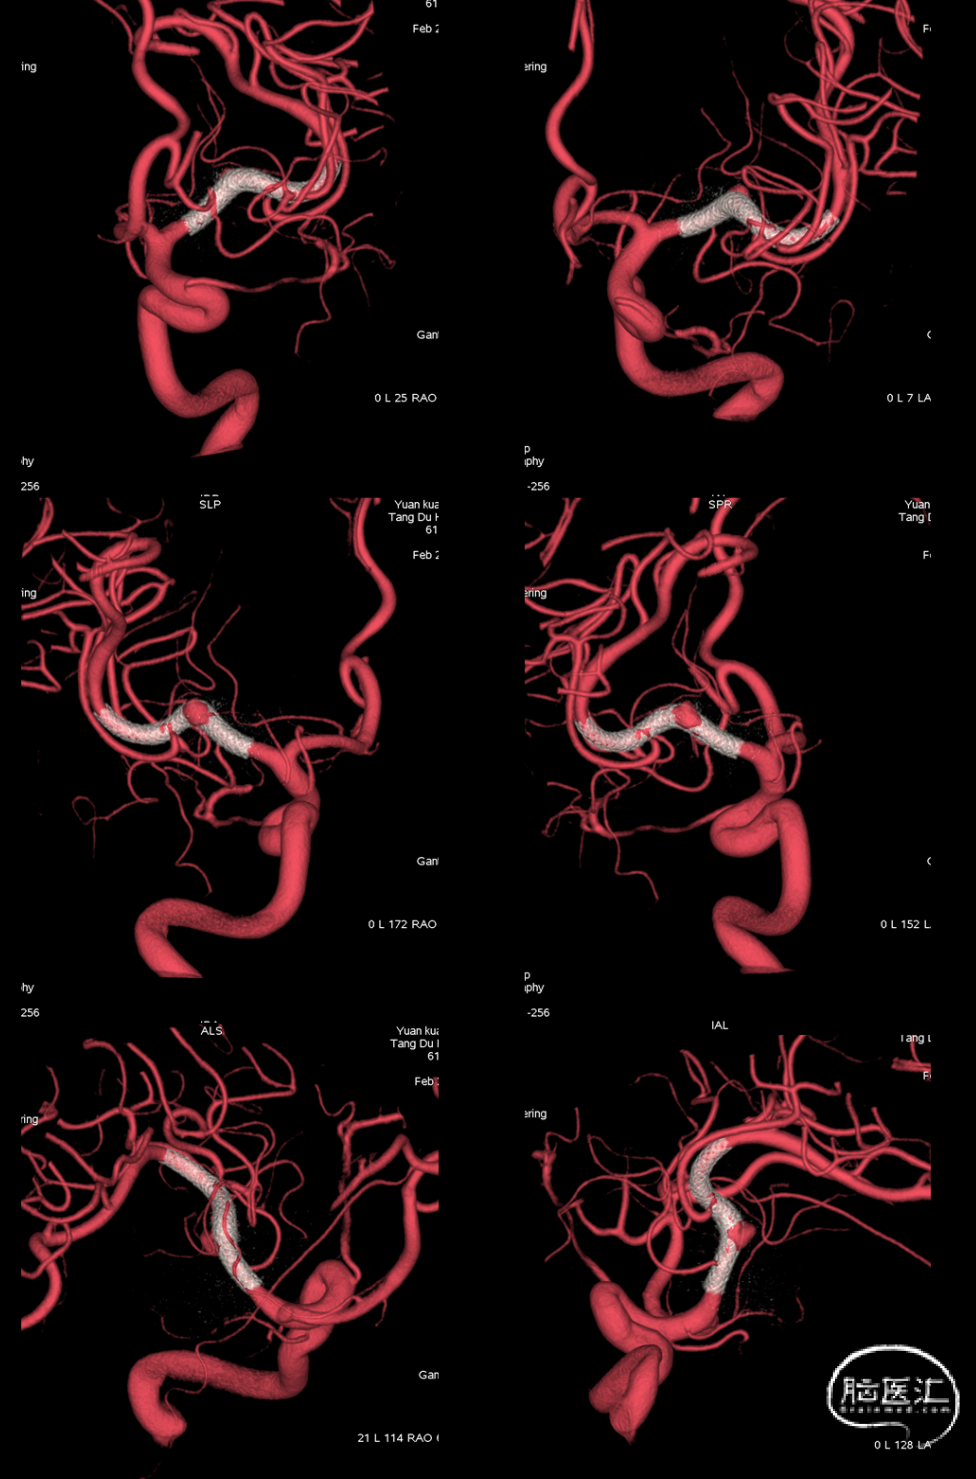

术中造影、减影像及3D-DSA可见支架打开充分。微导丝辅助将Phenom™ 27 微导管送至M3段尽可能远的位置,支撑导管送至M1段尽可能接近动脉瘤。

术中Dyna-CT可见支架打开充分且贴壁良好。

支架远端释放10mm,确认支架打开后整体回撤至计划铆钉点 利用推拉技术让支架在载瘤动脉内充分打开

最后支架尾端减张释放,减影像及Dyna-CT可见支架完全打开且贴壁良好

术中2-D造影可见远端血管通畅良好,晚期动脉瘤内造影剂滞留明显。(07-28)

动脉瘤明显缩小,仅小部分动脉瘤显影,3D可见支架打开充分贴壁良好。